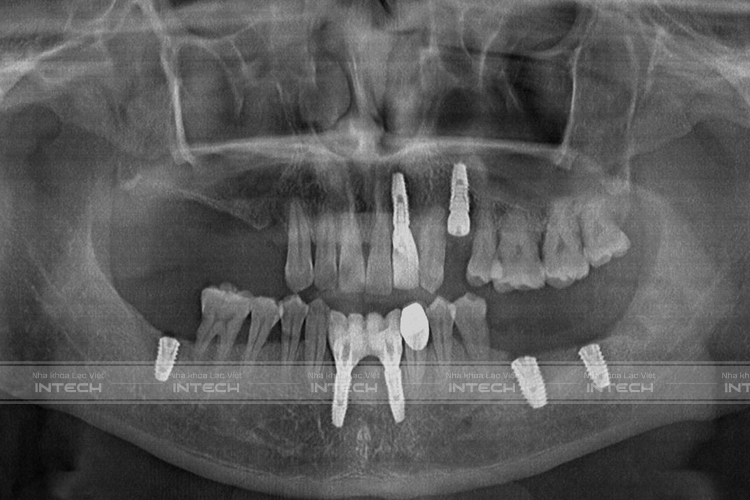

Hình ảnh phim chụp sau cấy ghép Implant của anh Mạnh (Ảnh: Nha khoa Lạc Việt Intech)

Kế hoạch điều trị bác sĩ đưa ra đó là:

• Nhổ bỏ các răng lung lay

• Cắm 10 trụ Implant: 5 trụ hàm trên và 5 trụ hàm dưới

• Xử lý toàn bộ vùng xoang viêm hàm trên